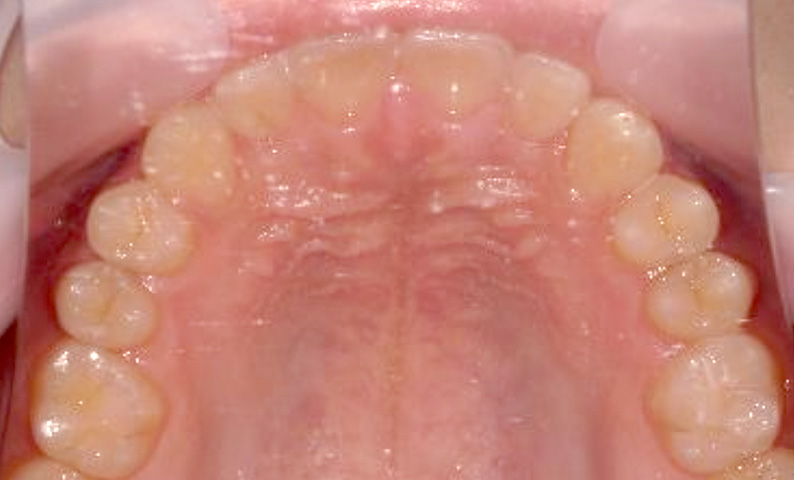

症例_025 上下顎の部分矯正

治療期間:13ヶ月金額:51万円+税女性前歯のガタガタ出っ歯

| Before | After |

|---|---|

|